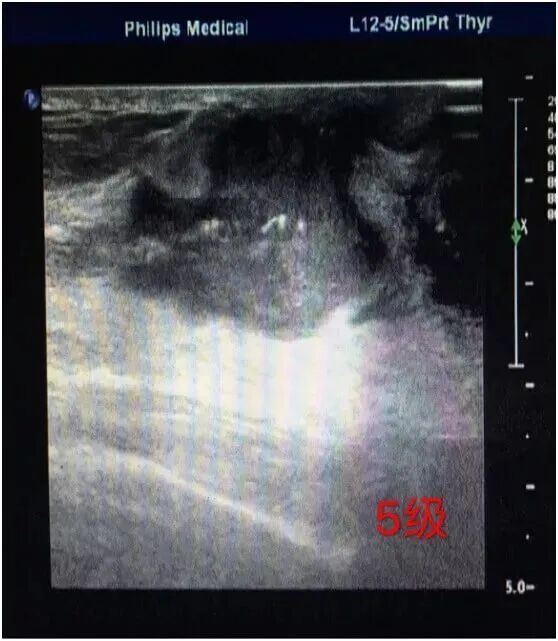

5级

用来表述几乎肯定是乳腺癌的病变。具有95%的恶性可能性。带毛刺不规则形密度增高的肿块、段或线样分布的细条状钙化,或者不规则形带毛刺的肿块且其伴随不规则形和多形性钙化是归于5级。建议手术活检。